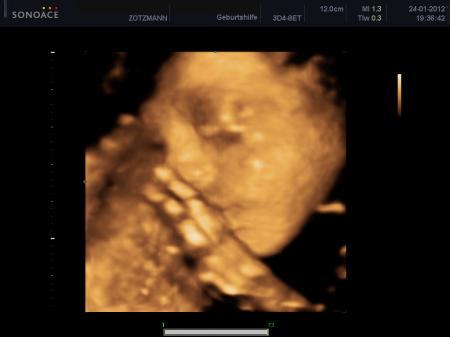

Hallo ihr Lieben, also meine Schilddrüsenwerte habe ich vor zwei Wochen checken lassen und da waren sie top. Vllt. ist es auch Streß und alles, ich weis nicht. Von der Ex kam wirklich nich mal was... Haha mein Freund ist ja Autolackierer und sie weiß, dass er darauf anspringt, wenn iwas mit Autos ist und da fragt sie, ob er am nächsten Tag Zeit hätte, sie hätte bei ihrem neuen Auto was mit dem Lack, aber weiß nicht, was das ist. Jaja, klar... Mal sehen, dass ist jetzt eine Woche her. Bis jetzt kam wöchentlich eine Anfrage nach einem Treffen! Ich warte diese Woche schon drauf! :) Liebe Grüße P.S. Hier noch ein Bild unserer Prinzessin!

Bild zu